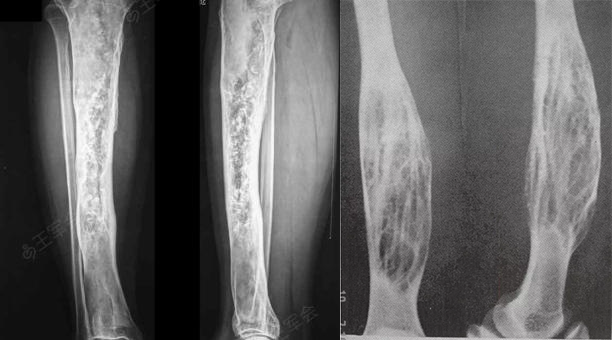

单骨多发型和多骨型病灶则发生任何骨,受累范围广泛,无硬化边,常伴有骨骼增粗变形、弯曲。

在剩下的 20-30% 的病例中,涉及多个骨骼。

常为单侧和单肢的发生病变骨所占比例: 股骨:91% ;胫骨:81%;骨盆:78%;脚:73%;肋骨;头骨和面部骨骼:50% ;上肢;腰椎:14% ;锁骨:10% ;颈椎:7%